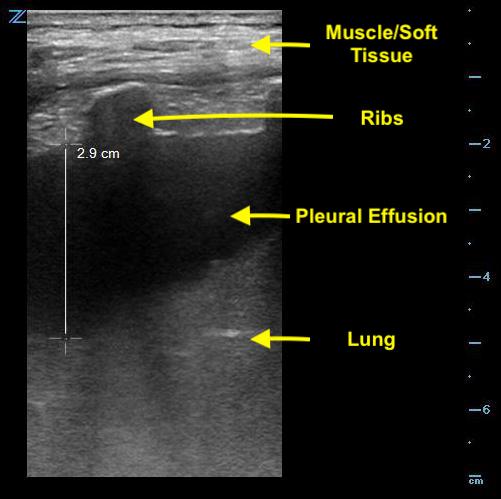

- Look for the deepest pocket of fluid superficial to the lung.

- Freeze the image and take note of the maximum permissible depth of needle insertion; this will prevent puncturing the lung. (Fig. 3)

- Bear in mind that the lung is a moving structure and that the depth of fluid may vary with respiration.

- Figure 3. Measurement of depth to lung parenchyma